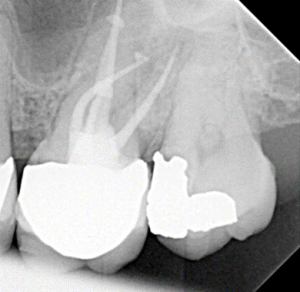

Root Canal / Retreatment

Apical Microsurgery / Apicectomy

Clinical Cases